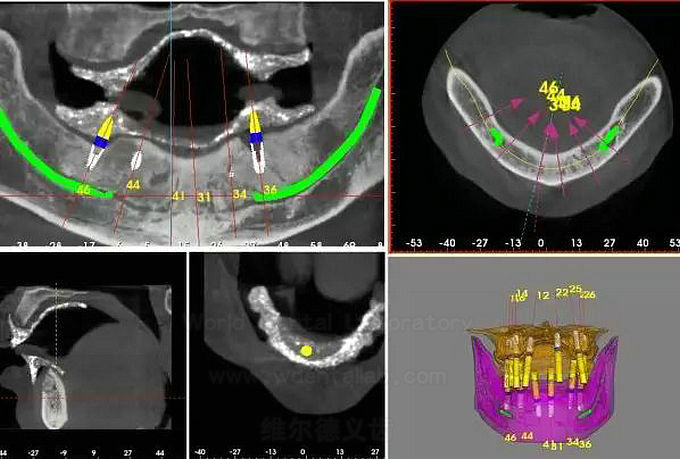

CAD/CAM Implant Surgical Guide